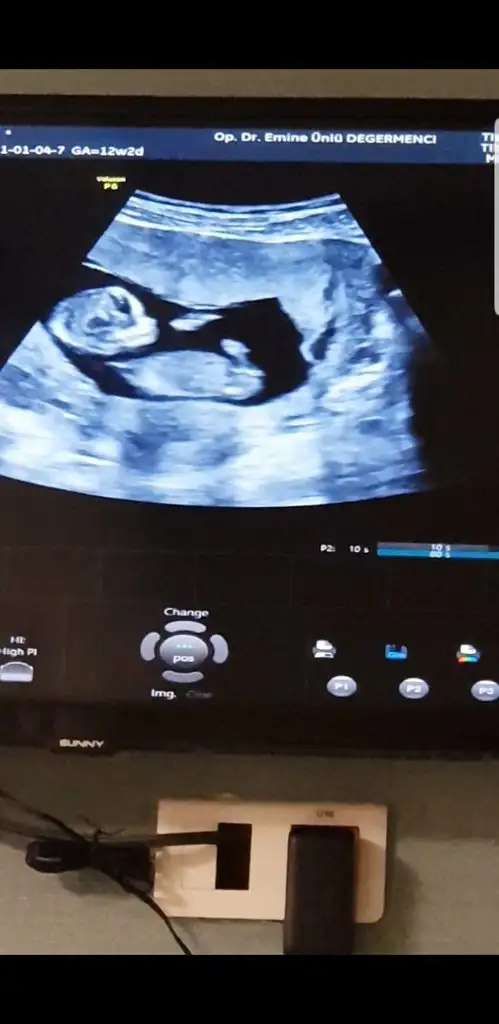

• WhatsApp Image 2021-02-13 at 12.57.28.webp

WhatsApp Image 2021-02-13 at 12.57.28.webp

19,2 KB · Görüntüleme: 101